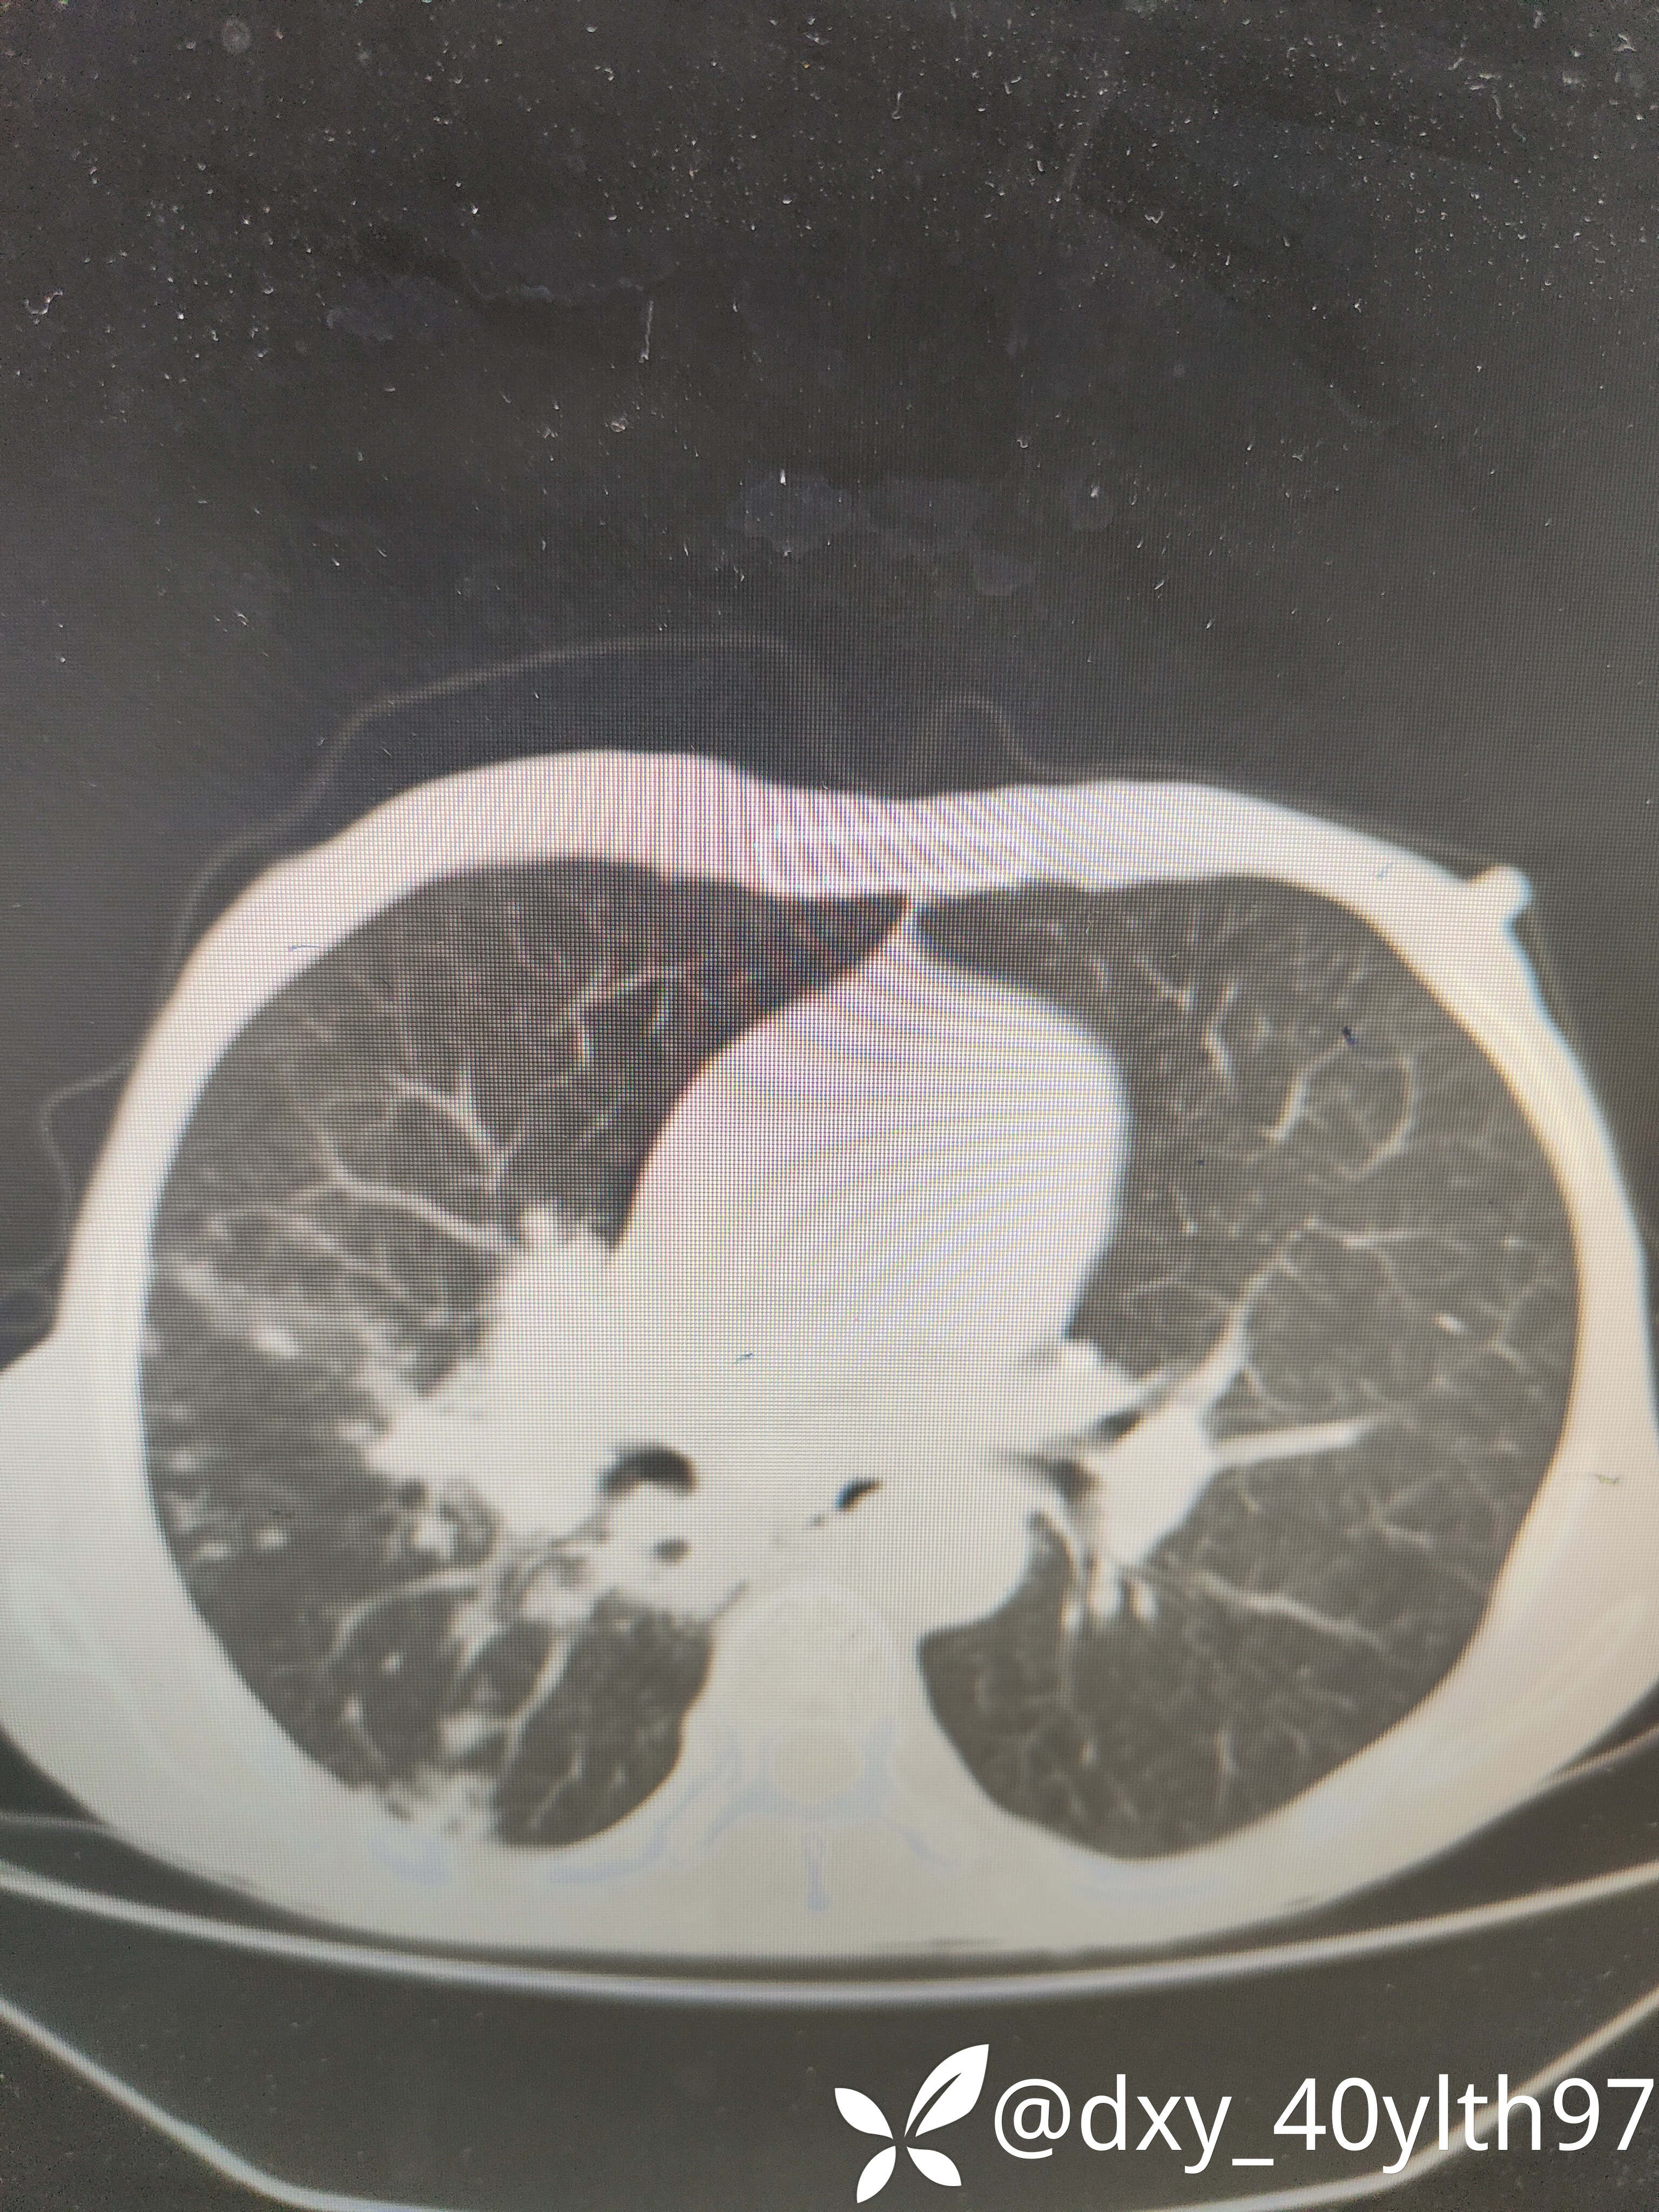

2021年5月首次肺部CT平扫,影像报告提示1.两肺慢性支气管炎、肺气肿、多发肺大疱;2.右肺中下叶多发感染性病变、结节、右肺门增大,建议治疗后复查或进一步检查排查右肺门区肿瘤性病变;3.左肺上段舌叶散在炎性病变

2021年8月因2型糖尿病入院复查肺部CT平扫,影像报告提示:胸部CT复查:1.右肺中下叶感染范围较前相仿、密度增高;2.右肺门区病变较前有所增大;3.右肺外基底段结节较前吸收。

2023年8月肺部CT平扫影像结果提示:1.右肺上叶密度增高影较前显著增大,建议进一步检查;2.两肺多发斑片结节灶较前增多,部分增大。

肺部增强CT影像学提示:右肺内大片不规则影轻度强化,肿瘤可能。